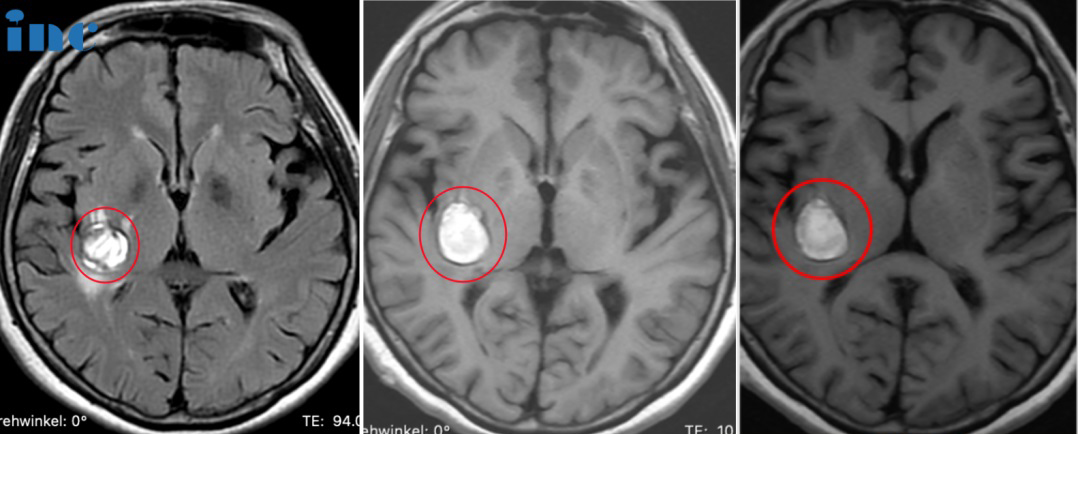

患者情況:30歲的萱萱2023年3月查出中腦及橋腦右側(cè)占位海綿狀血管瘤繼發(fā)出血。當(dāng)?shù)蒯t(yī)生考慮手術(shù)風(fēng)險大,偏癱幾率大,建議保守治療。和很多年輕的腦干海綿狀血管瘤女性患者一樣,當(dāng)她們步入婚姻自然的要迎接新的小生命。但這一直虎視眈眈的腦干海綿狀血管瘤一旦伺機(jī)而動如出現(xiàn)急性腦干出血,而致患者和胎兒于困境中,又該怎么辦?萱萱多方打聽之后,了解到在腦干海綿狀血管瘤治療領(lǐng)域一位國際神外教授巴特朗菲教授。

治療過程:9月27日,在蘇州獨墅湖醫(yī)院,巴教授順利全切手術(shù),手術(shù)后無癱瘓、無視神經(jīng)損傷、無呼吸控制和昏迷風(fēng)險。

30歲女士萱萱——腦干-中腦及橋腦海綿狀血管瘤手術(shù)

術(shù)后情況

術(shù)后當(dāng)天巴教授前往ICU查房時,已拔除氣管插管、已蘇醒。萱萱感激說道:“I can see,I can feel,I can move,I have power.”術(shù)后一天查房時,萱萱激動地說:“That’s amazing,I feel normal,as the same as(I did the surgery before).So amazing.(這太神奇了,我感覺我和正常無異,和術(shù)前無癥狀時一模一樣。太神奇了)”

術(shù)后4天查房,恢復(fù)越來越好的萱萱問道自己術(shù)前很關(guān)心的問題——能不能準(zhǔn)備順利備孕,“Can I safely prepare to have a child?”“I think so,yeah”,巴教授告知萱萱腦干海綿狀血管瘤已經(jīng)全切了,備孕可以的。

術(shù)后6天,萱萱下地行走自如,巴教授檢查了萱萱的手術(shù)切口,開心跟萱萱說“very good,even nobody can see”,萱萱也和愛人一起為巴教授點贊,合影留念。目前已出院。